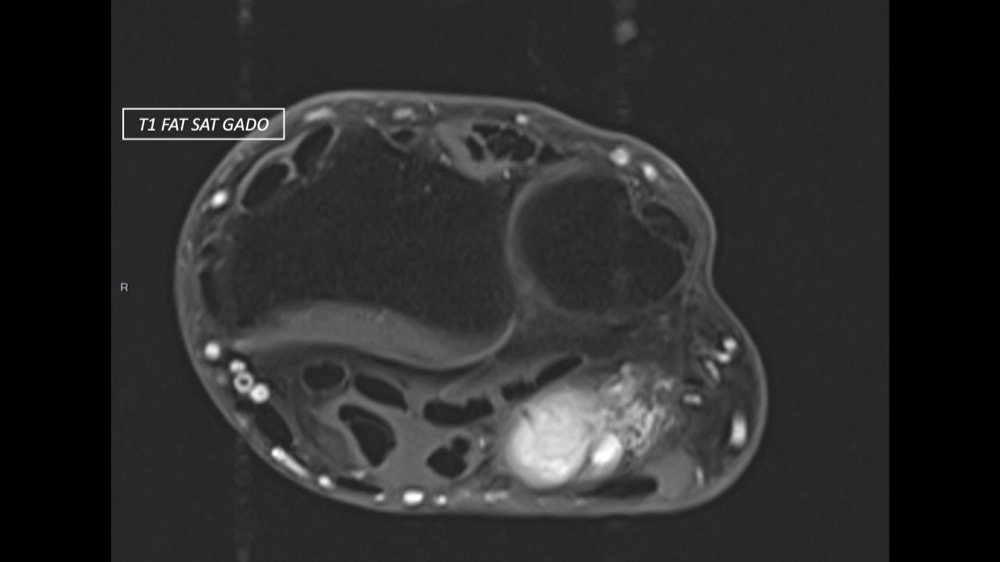

Dupuis / Benoist / Leclerc / Bousson 18/05/2022